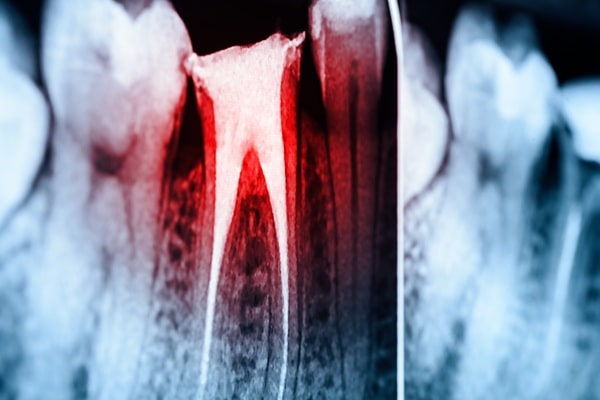

A dentist can see a lot during an exam, but not everything. Cavities often hide between teeth, infections can develop at the roots, and bone loss doesn’t show up until it’s advanced. That’s where digital X-rays come in. They give us a picture of what’s happening below the surface, so we can catch problems earlier and plan treatment with more certainty.

Taking a digital X-ray is simple. A small sensor is placed in your mouth, the image appears on a screen within seconds, and your dentist walks you through what they see. The process is fast, comfortable, and uses less radiation than older film systems.